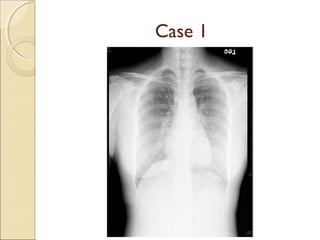

A resident in radiology presents two interesting cases: the first involves a harmatoma, and the second concerns a patient with double superior vena cava and tracheal bronchus. Both cases provide learning opportunities for radiology residents to recognize rare anatomical variations and abnormalities.